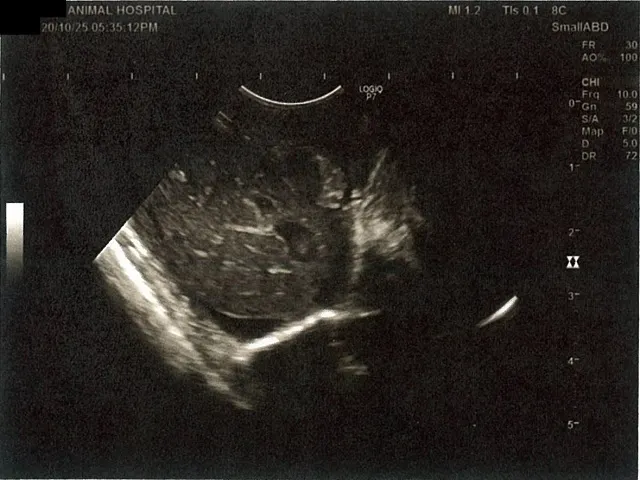

《心臓周りの胸部以外の全ての腹部で腹水がみられるとの診断です》

大網という部分で内臓を包む膜のようなものです。その周りに腹水が溜まっています。

右腎臓周りに腹水が確認できるエコー写真